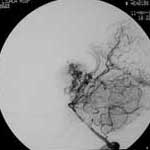

二、脑动静脉畸形(AVM)

---- Spetzler对AVM的分级方法已越来越多地被人们接纳和采用。脑AVM最危险的症状之一是出血。AVM每年的出血率为 3%~4%,第一年内再出血约6%。每次出血的致残率为30%,病死率为12.5%,而积极治疗的总残废率加病死率在10%以下。

---- 血管内栓塞对于单支或少数供血动脉的AVM,特别是新近出血的病例,可以达到微侵袭、痛苦小、疗效迅速的目的。 近来改变栓塞方式,将导管直接放置 畸形血管团内,注射NBCA胶,可使畸形团的解剖 治愈率提高至27%。再加上更细、超 滑的微导管问世,栓塞的并发症更为降低。针对大型、功能区 的AVM栓 塞可缩小其体积,改善血液动力学分布,以利于显 微外科技术切除或放射外科治疗,是后二者的重要辅助手段。

----立体定向放疗(γ-刀、χ-刀)对AVM是一种有希望的选择性治疗方法。据文献报道,AVM治疗后年消失率30%~50%,2年 消失率70%~90%,其消失速度与所用的照射量成正比,与AVM 的大小成反比。从治疗到AVM完全闭合之前每年的出血率 3%~4%,与自然出血史相同,所以对有出血史的患者,应优先采用栓塞或手术方法。大型AVM经若干次栓塞后体积缩小即可 放射治疗。但栓塞物质应是NBCA。其它颗粒或丝线栓塞,均有复发之虞。栓塞加立体定向放疗可使60%~80%的患者免于开颅 手术而获治愈。